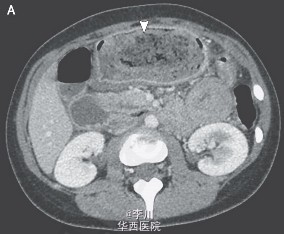

胃石症一例

主诉 病史

一位17岁的女孩因呕吐、腹痛48小时被送入急诊,该女孩患有自闭症和嗜毛癖。血常规和新陈代谢无特殊异常表现。腹部CT发现了端倪: